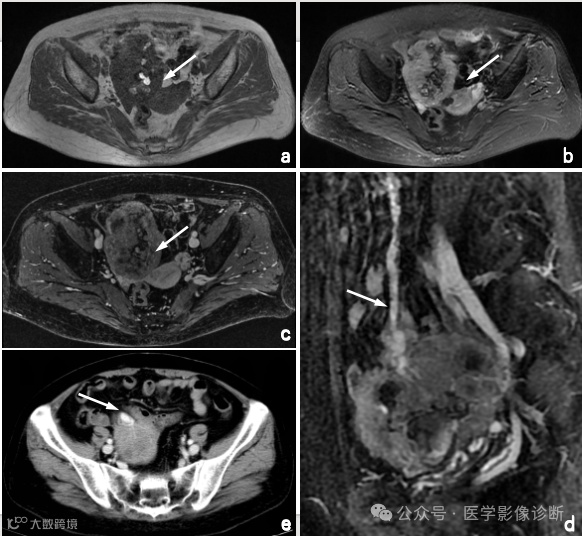

Case 3

患者,女性,57岁,盆腔肿物就诊于妇科,妇科医生诊断为卵巢肿瘤。

影像学表现

MRI扫描(a - c)显示盆腔肿块,T1WI呈出血样高信号,T2WI/FS内部呈低信号。增强扫描表示非均匀增强。肿块与小肠密切相关,增强MRI矢状面(d)和轴向CT (e)可见肠系膜大血管(箭头)供血,提示肠道原发病变。然而放射科医生受临床卵巢肿瘤的诊断干扰未能明确诊断为小肠间质瘤。